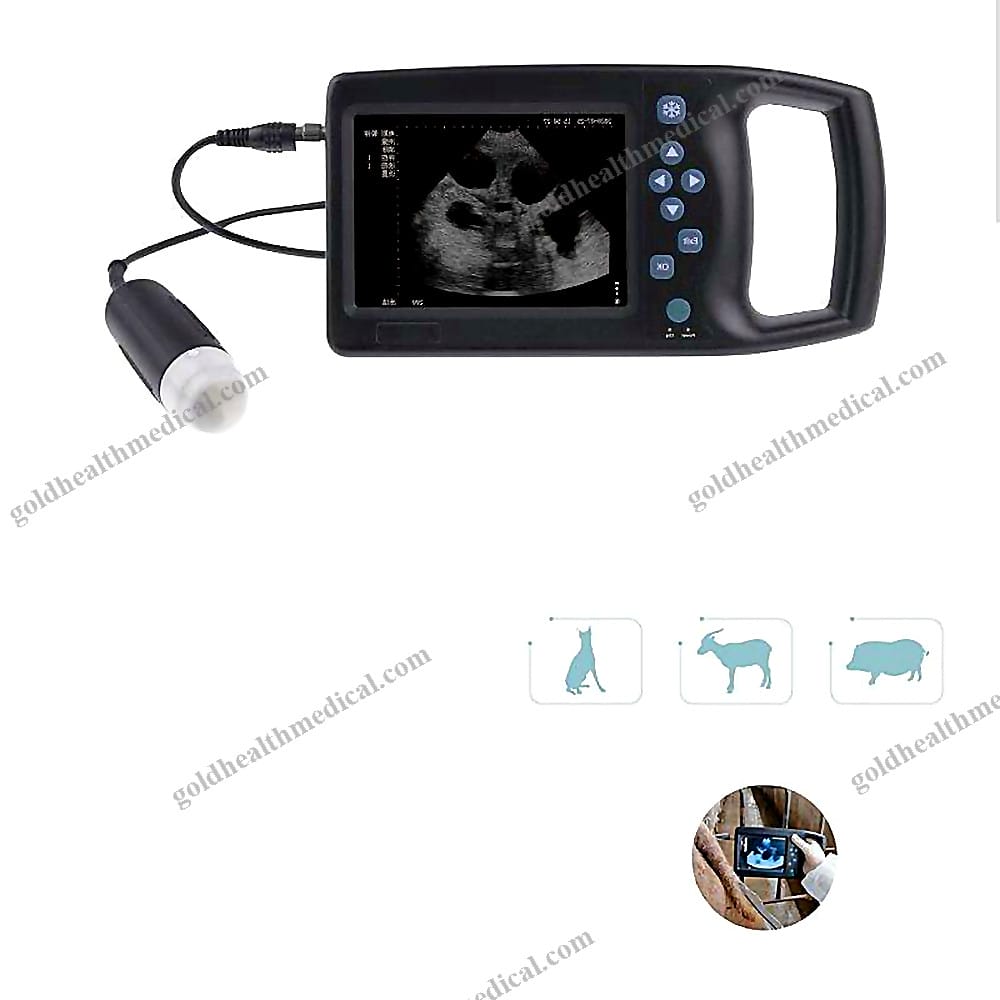

Portable Veterinary BUltrasound for Pregnancy Detection

Veterinary Ultrasound Machine

Introducing GoldHealth Medical’s state-of-the-art veterinary ultrasound machine, meticulously designed for animal hospitals, veterinary practices, and pet care facilities. Engineered with precision, this device is the ultimate solution for veterinarians and breeders seeking unparalleled imaging quality and versatility.

- Superior Imaging: Advanced B-mode technology delivers crystal-clear views of internal structures, ensuring accurate diagnosis and treatment.

- Broad Applicability: Ideal for pregnancy detection in pets, organ assessment in large farm animals, and health checks on exotic species.

- Portable Design: Compact and versatile, this machine is perfect for various settings, enhancing the quality of animal healthcare.

- Display Size: 5.5 inches

Product Name: Advanced Veterinary B-Ultrasound Machine

- Precision and Versatility: Designed for accurate pregnancy detection and comprehensive diagnostic imaging in animal healthcare settings.

- Portable and Reliable: Powered by a built-in rechargeable battery with a capacity of 2000 mAh, ensuring uninterrupted performance during field or clinic use.

- High-Quality Imaging: Equipped with a 5.5-inch display and 256-level grayscale for sharp, detailed B-mode, B+B, B+M, and M-mode imaging.

- Durable Construction: Crafted from high-grade plastic materials, built to withstand frequent use in demanding environments.

- Display Size: 5.5 inches.

- Display Modes: B, B+B, B+M, M.

- Image Grayscale: 256 levels for enhanced clarity.

- Ideal for use in animal hospitals, clinics, research labs, and mobile veterinary services.

- Suitable for a wide range of animals, including dogs, cats, horses, and other pets.

Applications by Animal Type:

- Dogs

- Cats

- Horses

- Other Pets

- Sleek and professional black finish.